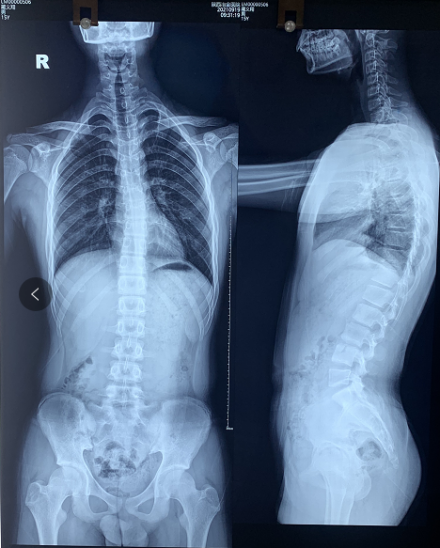

说着安主任就开始认真仔细地给患者进行查体,现症见:脊柱C型改变,左肩高于右肩,左背高于右背;X光片显示:T3-T3左凸右弯17度,诊断为“青少年特发性脊柱侧弯”收入我科进行治疗。

脊柱全长照片:

入院后脊柱侧弯矫形科安主任立即给患者完善了各项检查,并为他制定了个体化的全系统康复组合疗法,第一时间给予积极有效的治疗。

住院过程中最温暖人心的是彼此的信任和理解,所以飞飞经过不到1个月的治疗身体已经有了明显的改善,两侧腰背部平整度明显恢复,肌肉僵硬状态已好转,复查X线显示:脊柱基本居中,病情好转,予以出院。